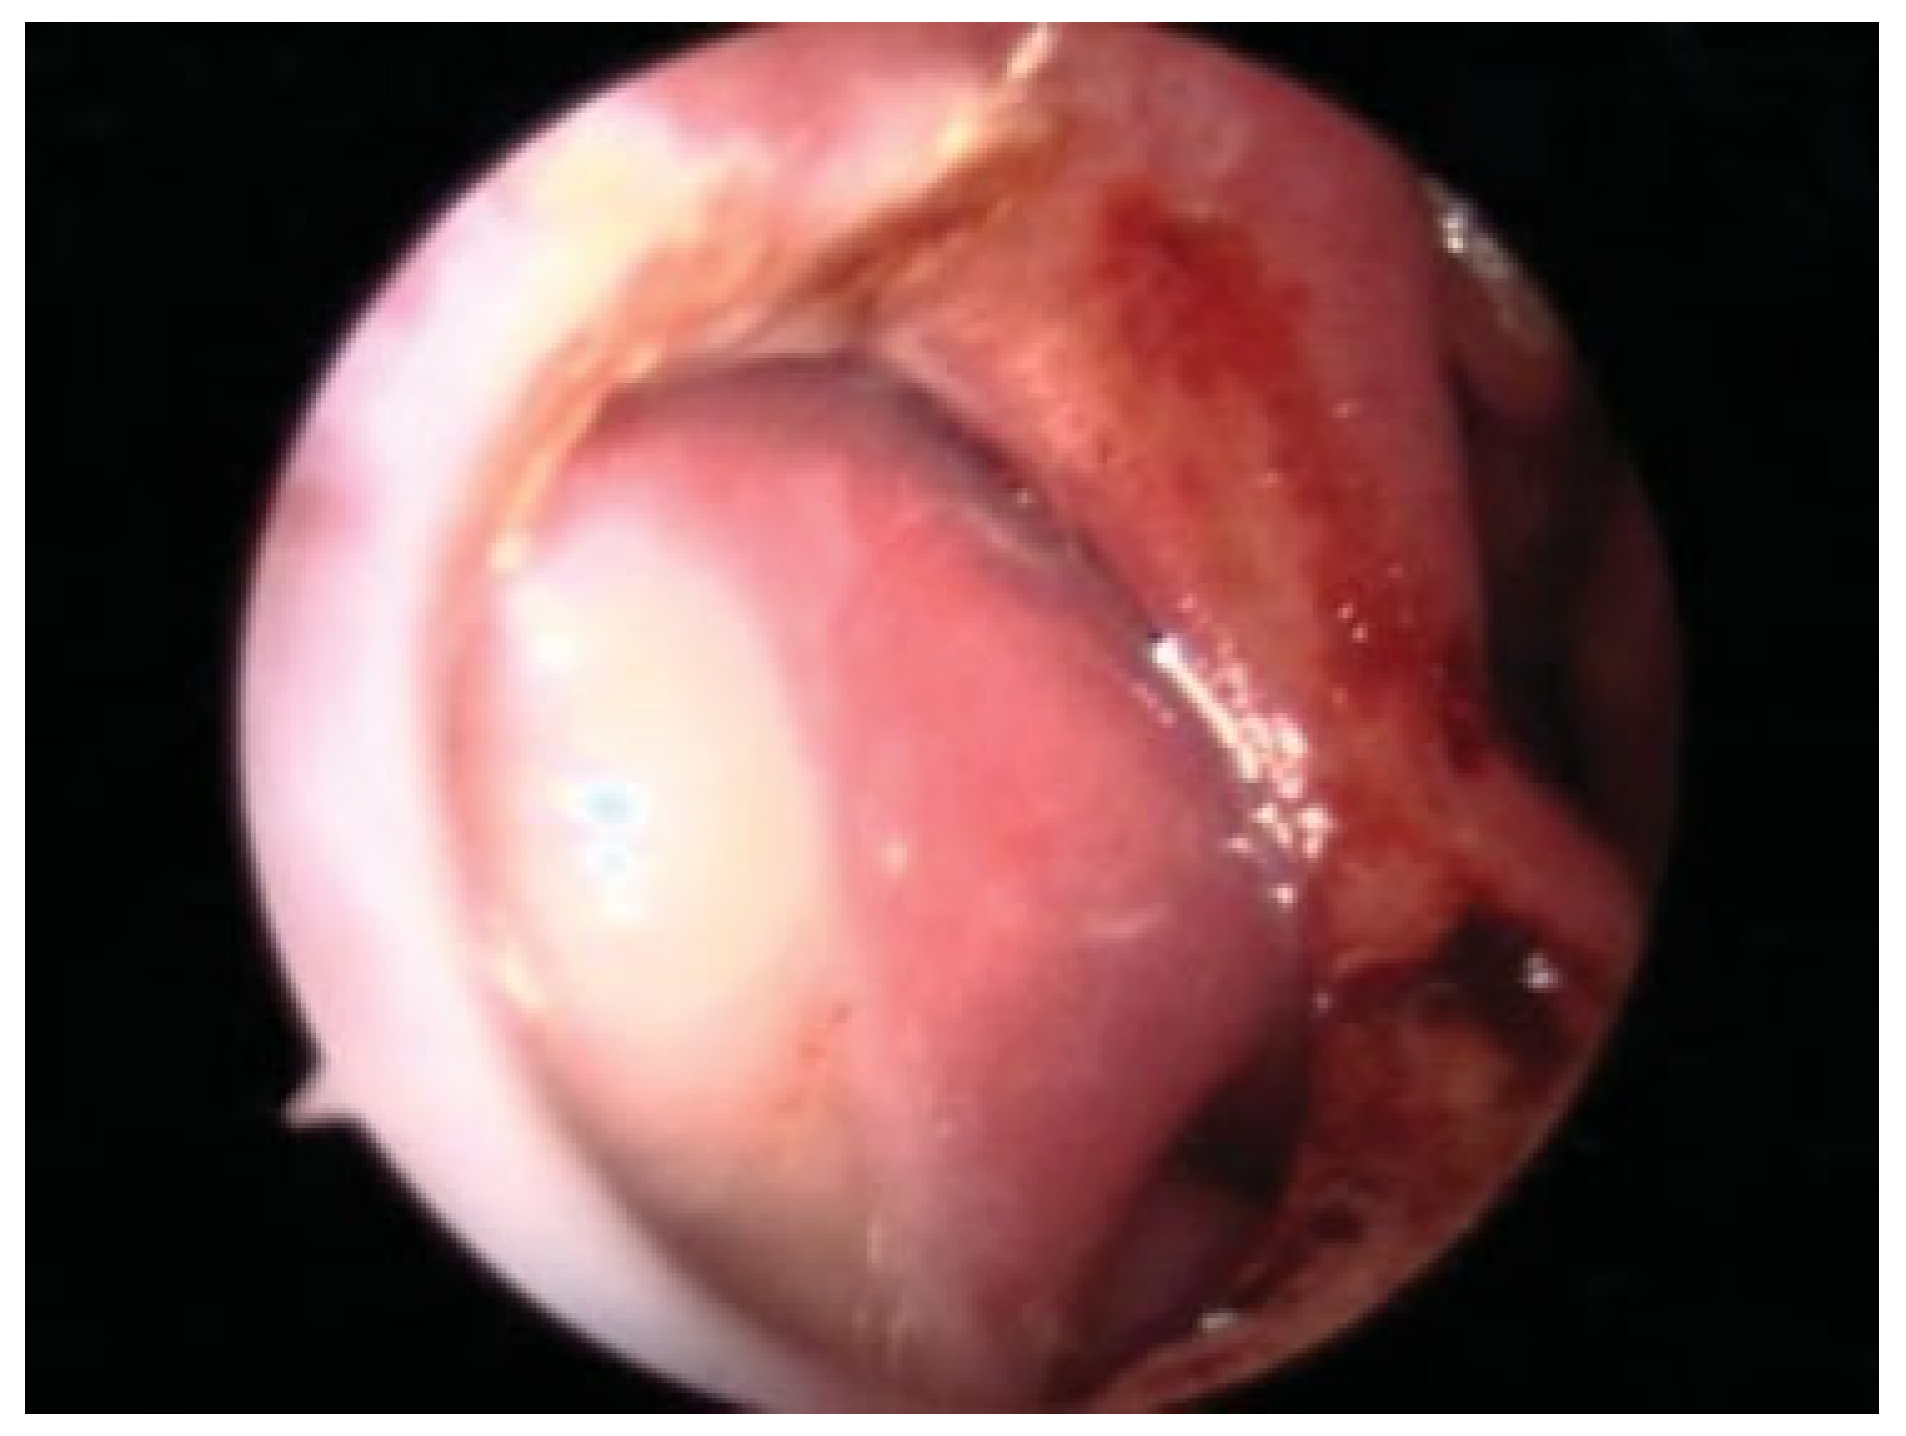

Figure 4. The pericranial flap has been elevated and is tunneled into the nasal cavity via a combined coronal and external rhinoplasty approach.

Figure 5. Demonstration of the length and orientation of the flap attained after dissection and tunneling through the nasal cavity prior to inset.

A rectangular pericranial flap pedicled on the supratrochlear vessels is designed (Figure 3) and incised with electrocautery, followed by elevation with a Cottle elevator. Through the external rhinoplasty approach, the nasal skin and soft-tissue envelope is then elevated superiorly in the subcutaneous plane and connected to the superior dissection. The tunnel is widened to 3 cm at the nasofrontal area appropriately and the flap passed through this into the nasal cavity (Figure 4 and Figure 5). The narrowest point is at the nasal dorsum at approximately 2 cm. Intra-operative laser angiography with the SPY system is performed to verify distal perfusion of the flap (Figure 6).